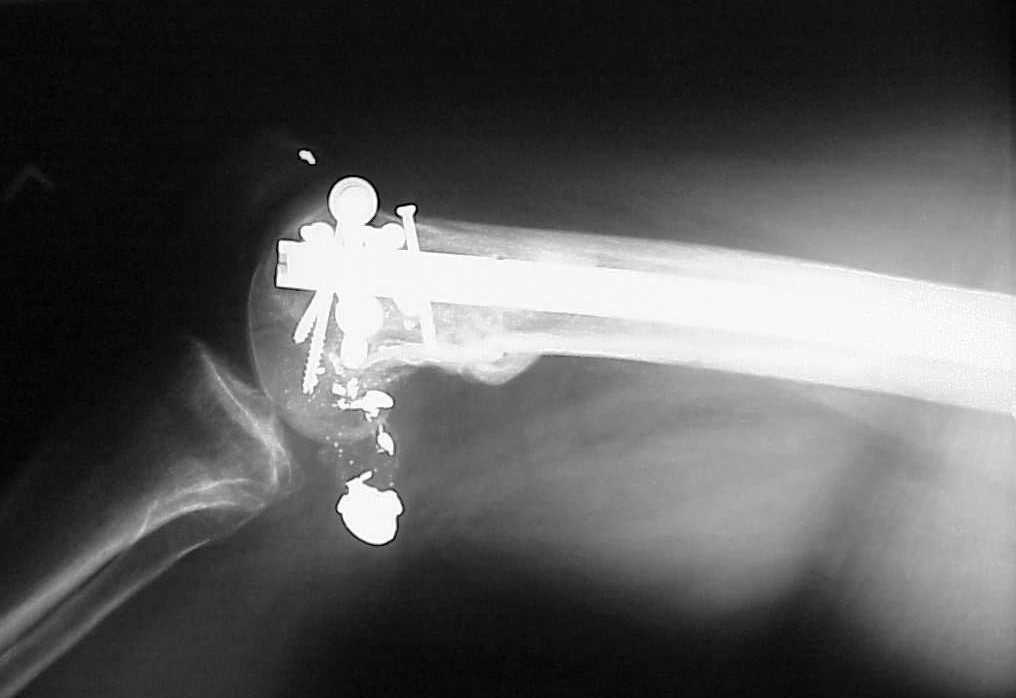

See attached case that was done several years ago before LISS. He had comminuted trochlea and anterior blocking screws were used to prevent anterior IMN cut-out.

Да, примерно так и сделали. Надо было, пожалуй, кончик гвоздя еще спилить, чтобы отверстие было еще дистальнее. Англоязычные коллеги еще

Since it was done closed the shaft will heal or at worst need an exchange IMN.

Nice job.

Мы пошли на операцию с планом попытаться сделать закрытый интрамедулярный, а не получится - сделать аппаратом. Посчитали, что получилось, хотя на еженедельной конференции ожидаются некоторые проблемы с объяснениями ;-)

Насчет стабильности для ранней нагрузки, конечно, сомнительно, но при таком повреждении ранняя нагрузка противопоказана в любом случае. Для ранних движений Должно хватить. Снимки в следующем сообщении.